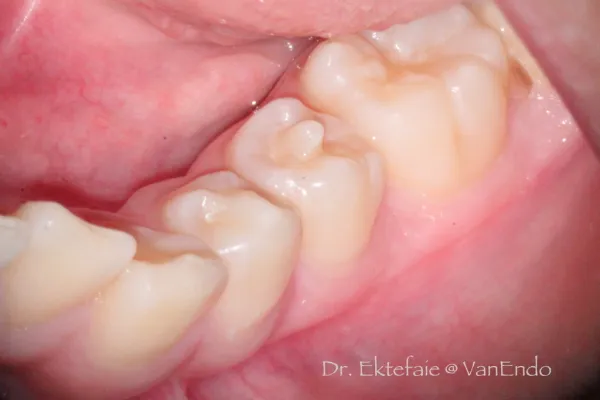

4. Dens evaginatus

Anomalous tubercle/ cusp projecting from occlusal surface – usually premolar

- Extra cusp worn down, predispose to tooth decay